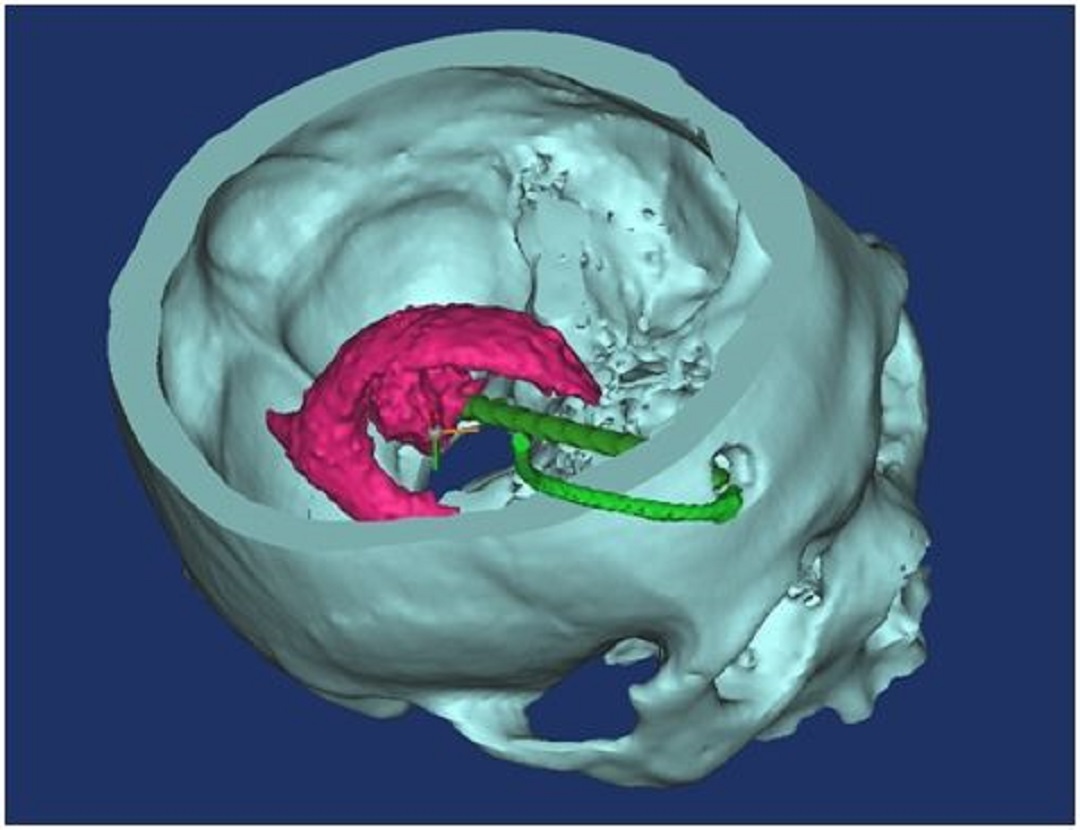

【術(shù)前制作導(dǎo)板】

首先采集患者的頭顱螺旋CT原始dicom數(shù)據(jù),將CT數(shù)據(jù)導(dǎo)入計算機(jī),運(yùn)用比利時醫(yī)療三維軟件,運(yùn)用3D重建頭顱面具模型,進(jìn)行血腫3D重建,在三維圖像上設(shè)計穿刺通道,調(diào)整通道在血腫的位置、通道與面具的交叉點,即為穿刺點位,將畫出的部分面具轉(zhuǎn)換成打印機(jī)能識別的gcode代碼,輸入3D 打印機(jī)打印,即為應(yīng)用于手術(shù)中的導(dǎo)航導(dǎo)板(如下圖):

穿刺路徑

導(dǎo)板與血腫